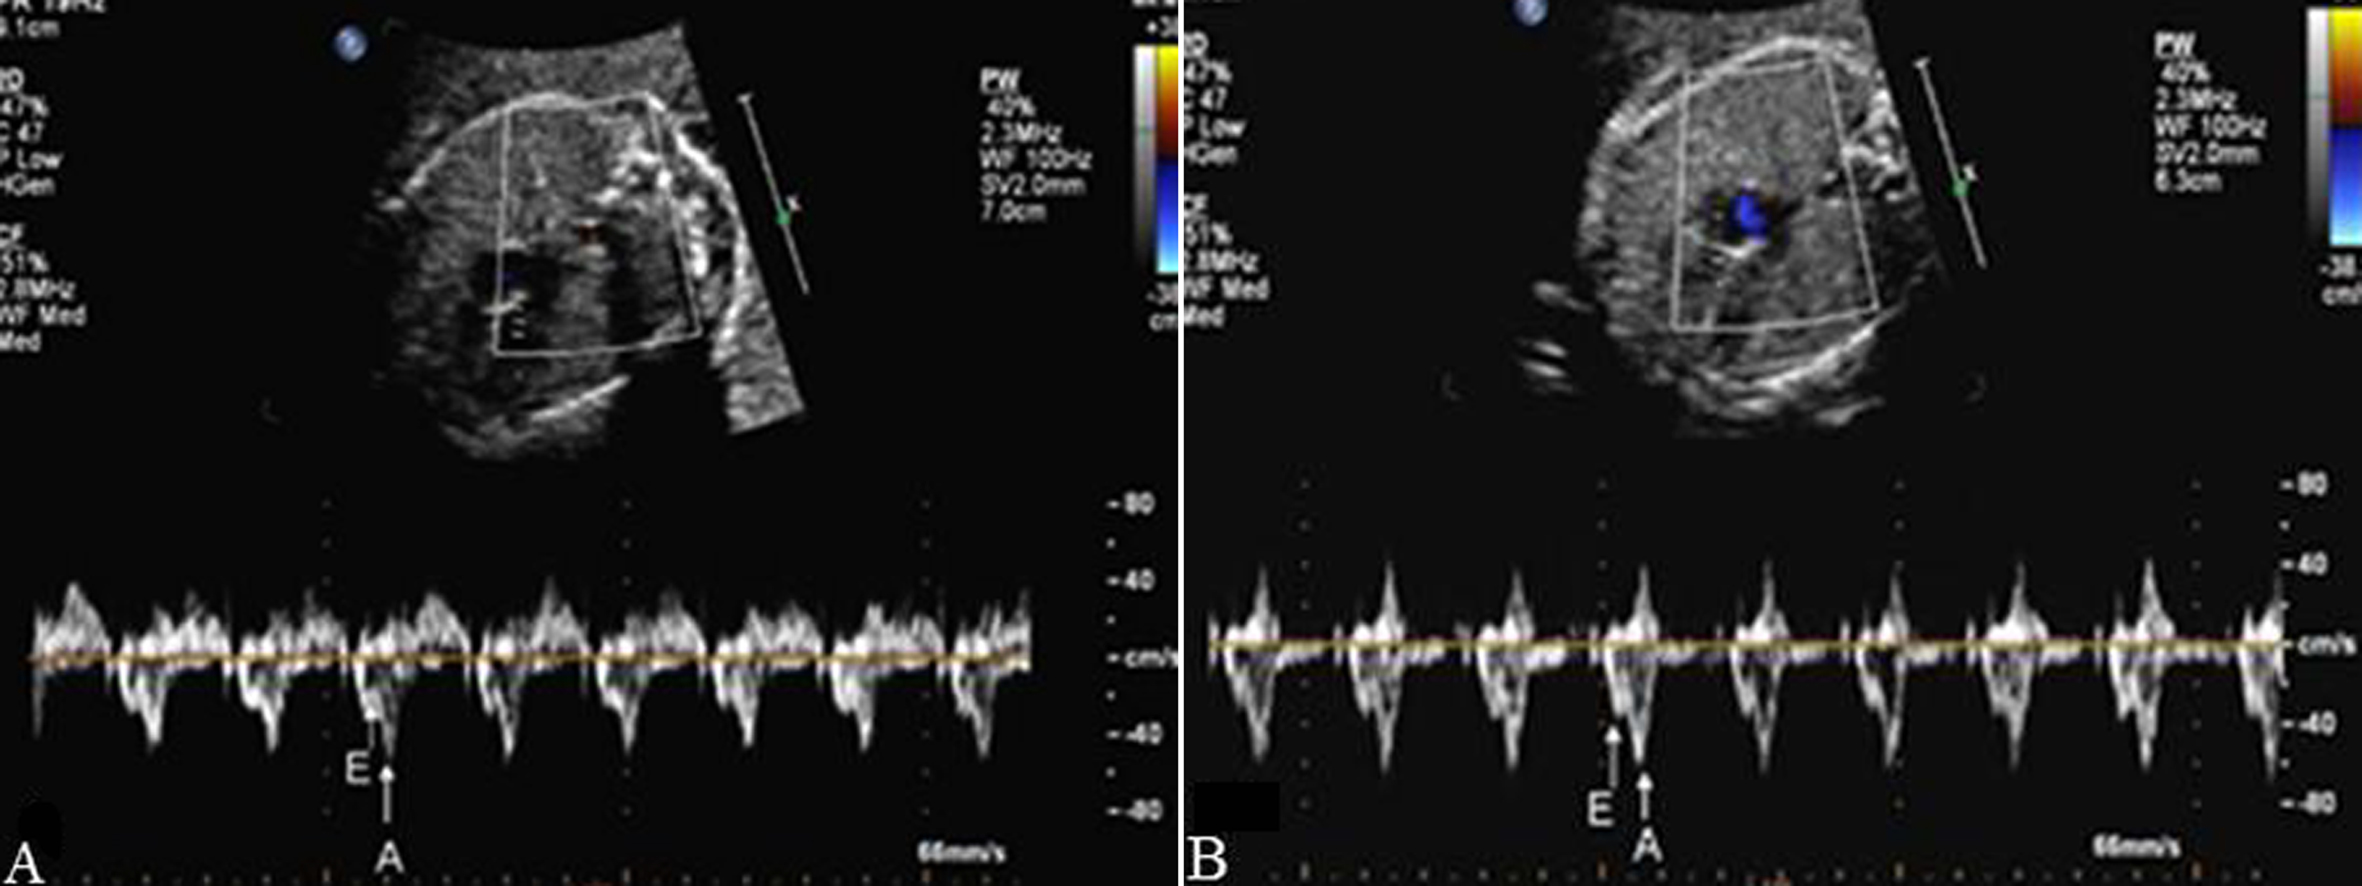

2.检查内容 观察彩色多普勒显示的过房室瓣、半月瓣、卵圆孔瓣的血流及各血管内(包括上下腔静脉、肺静脉、主动脉、肺动脉、主动脉弓、动脉导管弓、静脉导管等)的血流方向是否正常,有无反向血流或五彩缤纷、色泽镶嵌的高速血流信号显示。用脉冲多普勒测量过房室瓣、半月瓣血流、测量静脉导管内血流,以了解胎儿心脏节律情况、分析心房舒缩与心室舒缩之间的关系、了解胎儿的心功能等。正常胎儿房室瓣多普勒血流时间流速曲线呈双峰频谱,E峰小于A峰(图1);有时,三尖瓣血流可表现为单峰见切迹。半月瓣血流均呈单峰,多普勒时间流速曲线图显示肺动脉瓣血流收缩期射血时间大于主动脉瓣,峰值上升支亦快于主动脉(图2)。静脉导管为连接脐静脉和下腔静脉间的一段很短的血管,直径约为1~2mm,应用彩色多普勒可发现脐静脉血流至此处时,流速增快,呈花色血流信号(图3)。正常胎儿静脉导管的血流频谱呈连续单向双期双峰血流频谱, 有两个波峰两个波谷,第一个波峰“S”峰(房室瓣的关闭下移导致心房压的下降),第二个波谷“V”谷(心室等容舒张房室瓣上移导致暂时的心房压上升),第三个波峰“D”峰(为心室舒张房室瓣开放,血流快速流入心室导致心房压下降),第四个波谷“A”谷(心房收缩)(图4)。

图1二尖瓣血流时间流速曲线(A)和三尖瓣血流时间流速曲线(B),E峰<A峰